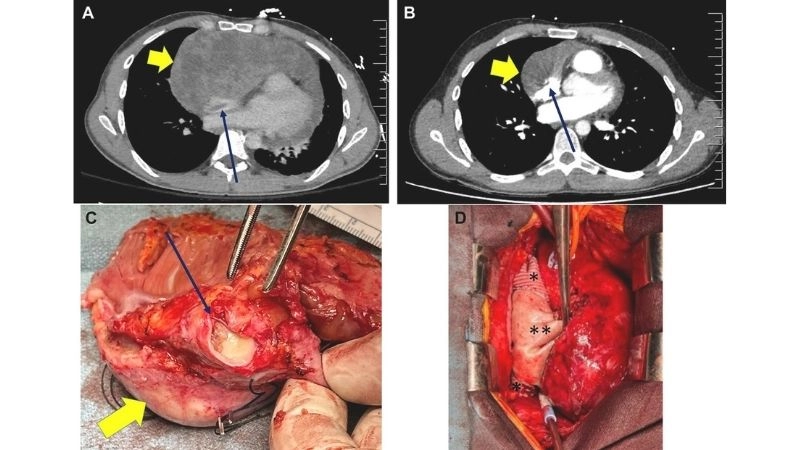

Images visual examples of cardiac sarcoma

Cardiac sarcoma is a rare malignant tumor that originates in the heart’s tissues, disrupting circulation and heart function. Visual examples often include MRI or CT images showing irregular masses within cardiac chambers.